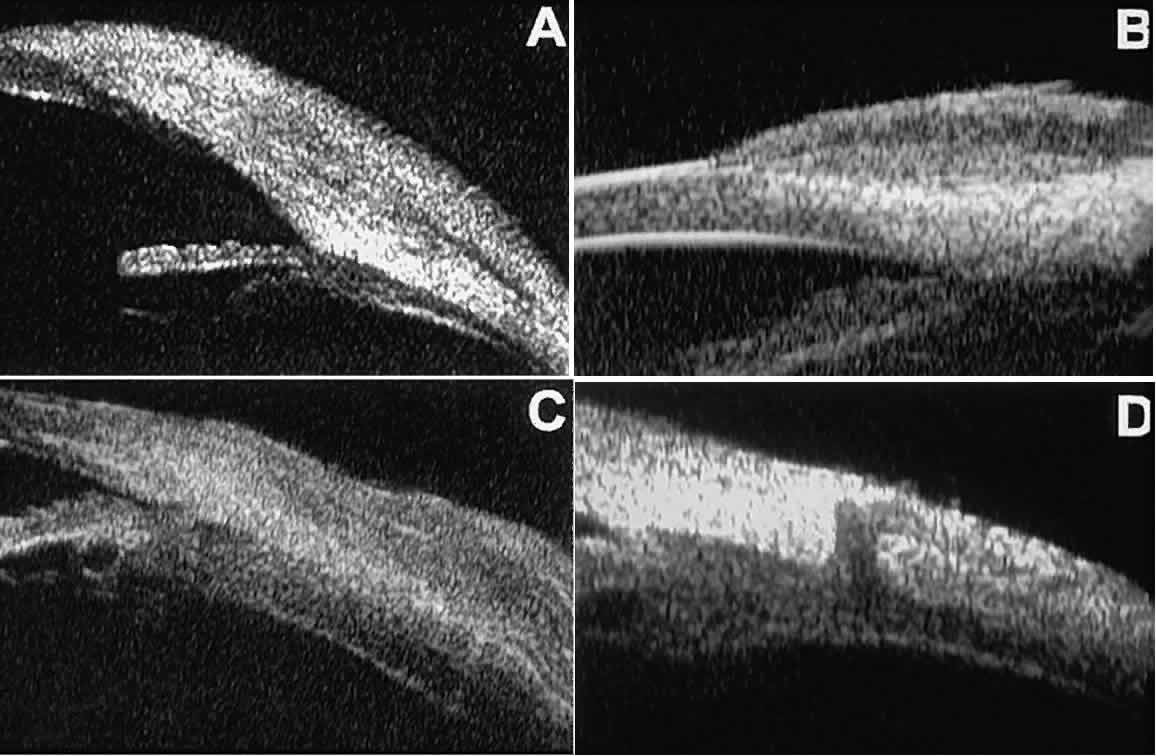

Cystic lesions of the iris and ciliary body can be of four types: primary neuroepithelial cysts, stratified squamous epithelial cysts, neuroepithelial cysts associated with solid tumors, and intratumoral cavities.15 Primary neuroepithelial cysts (see Fig. 22) are very distinct on UBM imaging. These lesions consist of a central sonolucent cavity surrounded by a thin wall of highly reflective neuroepithelial cells. They arise from the posterior surface of the iris (see Fig. 22A), in the iridociliary sulcus (see Fig. 22B and C), or from the inner aspect of the ciliary body (see Fig. 22D). They are often multifocal (see Fig. 22C and D) and bilateral.15 The largest lesions of this type typically occur in or near the horizontal meridians.

Stratified squamous epithelial cysts (Fig. 23) are almost exclusively unilateral and unifocal,15 have substantially thicker walls than do primary neuroepithelial cysts, and usually contain prominent intracavitary particles (desquamated epithelial cells). Almost all such cysts involve the peripheral iris and angle region. Such cysts are usually secondary to prior ocular surgery or laceration in which conjunctival epithelial cells were implanted into the iris stroma.

Fig. 23. UBM features of stratified squamous epithelial cysts of iris. A. Thick-walled implantation cyst of stratified squamous epithelium replacing normal iris. Note intracavitary particles. B. Bilobed stratified squamous epithelial inclusion cyst of iris with prominent intracavitary particles.

Secondary neuroepithelial cysts occur rather frequently in association with solid tumors of the iris or ciliary body.15 On UBM (Fig. 24), such cysts appear quite similar to the primary neuroepithelial cysts described above; however, they are associated with a solid mass arising within the iris or ciliary body.

Fig. 24. UBM appearance of neuroepithelial cysts associated with solid tumors of the iris and ciliary body. A. Single neuroepithelial cyst associated with iris melanoma. B. Multiple neuroepithelial cysts associated with iridociliary melanoma.